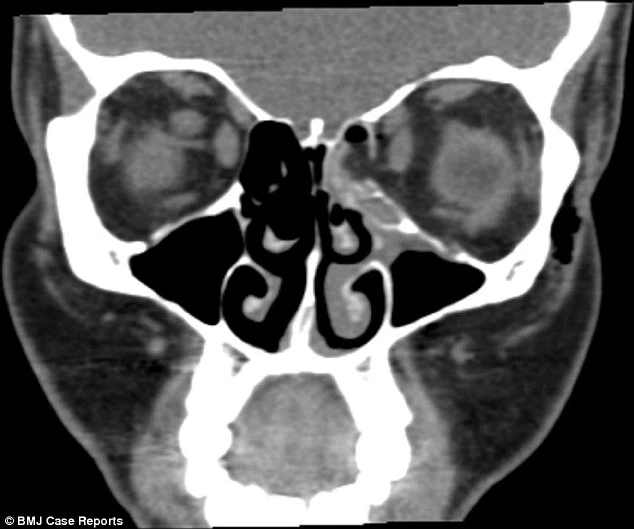

Phim chụp CT cho thấy bệnh nhân đã bị gãy một xương trong hốc mắt vì áp lực trong xoang quá cao khi hỉ mũi. Vết vỡ làm mỡ tràn vào đường hô hấp, khí bị kẹt trong mô quanh mắt.